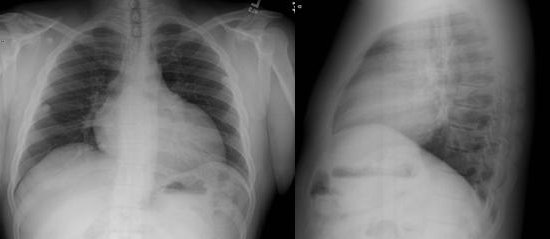

See chest radiograph in Figure 1.

Figure 1. PA and lateral chest radiographs from the patient. The images show mild elevation of right hemi-diaphragm, normal lung fields and cardiomegaly.